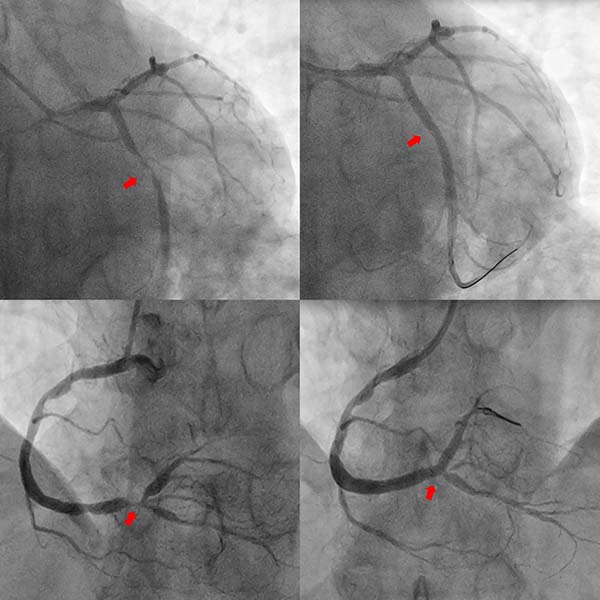

案例3

尹先生于2025年9月7日因结肠癌就诊于清华大学附属垂杨柳医院普外科,拟行结肠癌根治术。之前5年前曾因心绞痛于清华大学附属垂杨柳医院心内科行冠脉支架置入术。术前评估完善了冠脉CTA检查,结果提示:冠脉多发重度狭窄。遂由普外科转入心内科行冠脉造影提示患者回旋支、右冠脉重度狭窄,同期分别置入新型药物涂层支架,从心内科出院后1个月在普外科病房完成结肠癌手术。